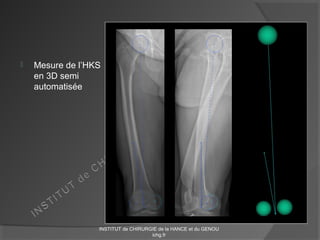

 Mesure de l’HKS

en 3D semi

automatisée